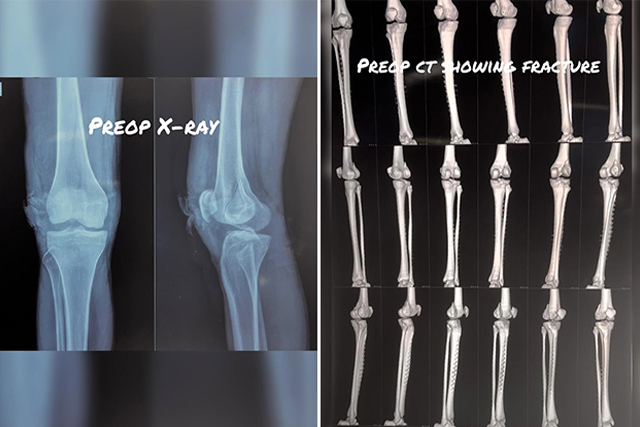

Open reduction and internal fixation (ORIF) for severe proximal tibia fracture

Open reduction and internal fixation (ORIF) for lateral condyle Hoffa's fracture